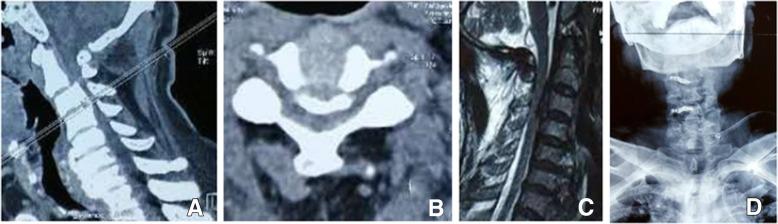

Analyses of effect factors associated with the postoperative dissatisfaction of patients undergoing open-door laminoplasty for cervical OPLL: a retrospective cohort study.

This study aimed to investigate the effect factors associated with the postoperative dissatisfaction of patients undergoing open-door laminoplasty for cervical OPLL.

In this study, 194 patients, who underwent open-door laminoplasty for cervical OPLL from January 2009 to January 2016, were retrospectively reviewed. The Patient Satisfaction Index (PSI) was collected at discharge, 6 months, 1 year, and the last follow-up. According to the PSI, patients were divided into satisfied group and dissatisfied group. The possible effect factors included demographic variables and surgery-related variables.